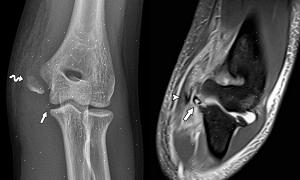

ברכיים

הברכיים הן אחד האזורים המושפעים לרוב מאימוני קרוספיט. למעשה, הפציעות הללו משפיעות גם על אנשי מקצוע וגם על טירונים, או על אלו שמתרגלים קרוספיט רק בשביל הכיף.

בדרך כלל, סוגים אלה של פציעות מופיעים עקב מיקום גרוע בזמן ביצוע התרגילים. עם זאת, ייתכנו גם בעיות גנטיות במפרקים שמביאות להופעתם.